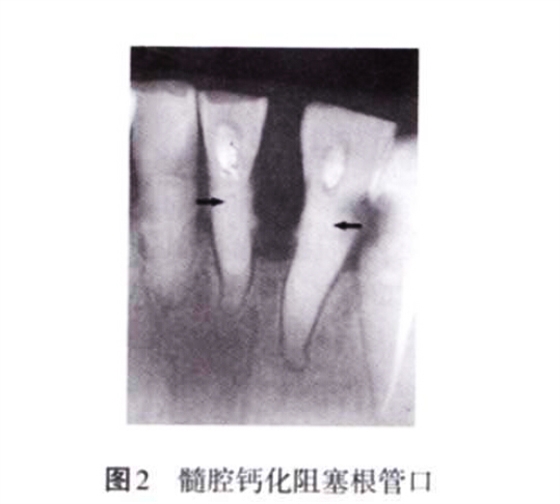

2. 2 未考慮髓腔的生理病理變化 髓腔的形態(tài)非一成不變,年齡的增長、外界物理和化學刺激、齲損等都會引起髓腔形態(tài)的改變,如髓腔體積變小、髓室頂和底的距離減小、髓腔鈣化阻塞根管口等,都會增加開髓難度(圖2)。術前如檢查不充分,未考慮髓腔的生理病理變化,并采取相應的治療措施,常會導致在尋找根管口的過程中破壞髓室底,甚至出現(xiàn)穿孔。

3. 2. 2 髓腔鈣化 生理性或病理性刺激都會引起髓腔部分或全部鈣化,部分鈣化主要表現(xiàn)為髓石形成(圖7)。